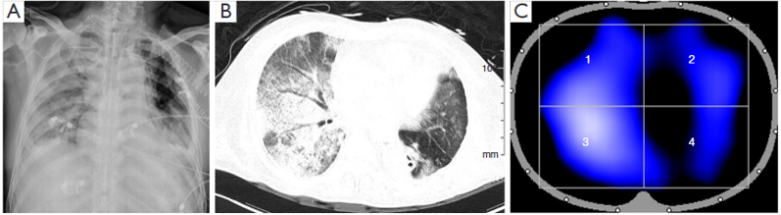

病例:男性,49岁,“颈胸腹三切口食管癌根治术”,术后出现食管胃吻合口瘘,胸腔感染,肺脓肿。右上肺叶切除。7月3日拔管后高流量吸氧,7月4日患者呼吸快,心率快,呼吸窘迫,48 h内再插管。胸片显示:双侧胸水,予以置管引流,右侧肺不张,支气管镜示左主支气管少许暗红色黏痰;右中下肺内见大量暗红色黏液。7月6日胸片见非手术侧(左肺)透光度降低,较前明显进展。7月7日胸部CT见右肺复张不全,左肺炎症渗出伴少量胸水(左侧较前片进展)。而当时EIT监测发现左肺通气良好,但此时患者氧合指数为97 mmHg,血管外肺水指数(ELWI)19 ml/m2,遂予插管及俯卧位通气,同时肌松(顺阿曲库胺)+镇静药物(咪达唑仑)+镇痛(瑞芬太尼)。7月8日俯卧位下,EIT发现右肺通气较前明显改善,左肺通气较前略有好转。此时氧合指数为290 mmHg,ELWI为10 ml/m2。7月9日胸片提示左肺渗出较前减少。7月13日经自主呼吸试验(SBT)顺利拔除口插管,神志清,对答切题。为何患者左肺渗出严重,但左侧通气良好呢?我们分析认为可能患者右肺是手术侧,术后有肺不张,导致其呼吸驱动增加;而左肺作为一个稍正常肺以及术中进行过单肺通气,导致左、右肺的顺应性不一致,在负压性的呼吸驱动过大时,左肺出现了负压性肺水肿。

图片

7月7日EIT

7月8日EIT

针对该病例的情况,笔者团队也开展了一项单中心回顾性研究,纳入了肺癌手术(肺叶切除术)后需要呼吸支持且患有严重低氧血症的患者,结果发现出现非术侧肺损伤的患者死亡率比较高。

图源:J Thorac Dis, 2023, 15(10):5574-5584.